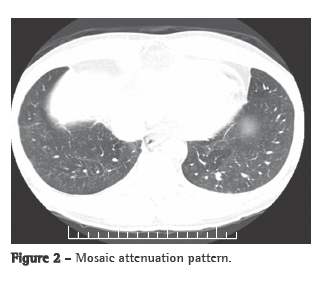

A transthoracic Doppler echocardiogram, which had been performed previously, showed moderate right heart enlargement, and pulmonary artery systolic pressure (PASP) was estimated to be 76 mmHg. A transesophageal echocardiogram demonstrated extensive thrombosis in the pulmonary artery trunk and PASP of 57 mmHg. Ultrasonography of the lower limbs revealed no signs of deep venous thrombosis. Lung perfusion scintigraphy, which was performed during hospitalization, showed low uptake in the view of the anterior and the apical-posterior segments of the left lung. The right lung was not visualized. Angiotomography of the chest revealed a large filling defect in the mediastinal and pericardial portion of the pulmonary trunk and arteries, there being enhancement of that defect after intravenous administration of contrast material (Figure 1a). In addition, there were predominantly peripheral nodules on the left (Figure 1b), as well as thickening of interlobular and peribronchovascular septa on the right, associated with upper lobe consolidation, moderate pericardial effusion and a mosaic attenuation pattern (Figure 2).

The clinical profile, together with the age of the patient, the failure of anticoagulant treatment, the tomographic alterations and the contrast enhancement, led to the hypothesis of intimal sarcoma-angiosarcoma-with pulmonary metastases. A CT-guided transthoracic biopsy of the left lung nodule was required. The specimen obtained consisted of a soft, reddish-tan filiform fragment, measuring 1.2 cm in length.